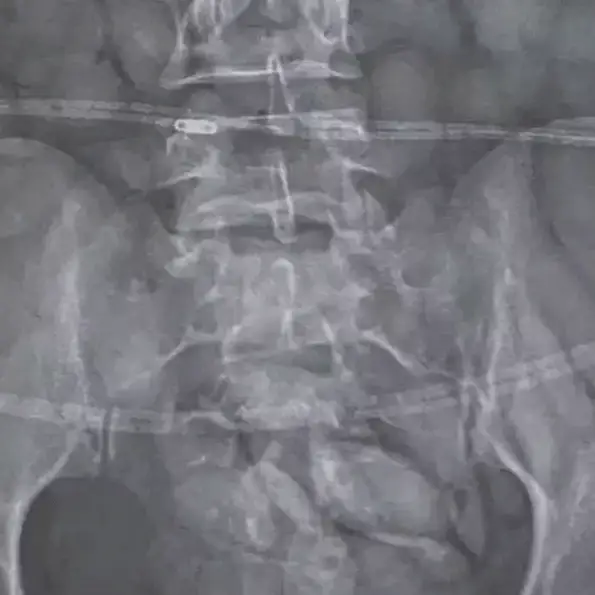

So, when the 30-year-old arrived, she was arrested and an X-ray instantly detected a number of foreign objects in her stomach.

Brig Athlenda Mathe, a spokesperson for the police, said: "The team immediately intercepted the drug mule as she was making her way through immigration. She was immediately arrested, taken to a local hospital where a medical X-ray confirmed and detected foreign objects in her stomach.